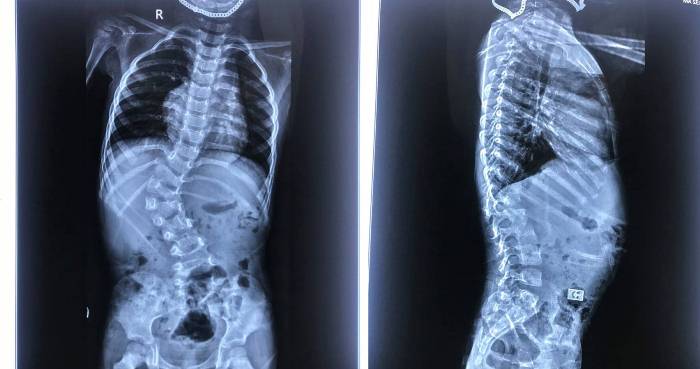

3 bệnh nhân là Ngô Phương Th (17 tuổi, ở Vĩnh Phúc), Vũ Thị Minh H (14 tuổi, ở Hải Phòng) và Phan Thanh Quang N (16 tuổi, ở Hà Nội) đều bị cong vẹo cột sống. Bệnh nhân Phương Th và Minh H đều được điều trị phục hồi chức năng, mặc áo chỉnh hình nhưng góc vẹo cột sống vẫn tăng dần, trong khi bệnh nhân Quang N chưa điều trị gì.

3 bệnh nhân trên đã được GS Arun Ranganathan - Giám đốc Trung tâm London Spine Care, BS phẫu thuật của bệnh viện St BartholoMew's và Bệnh viện Hoàng gia London cùng các chuyên gia của Khoa Chấn thương chỉnh hình và cột sống nắn cong vẹo bằng hệ thống vít trượt streamline hiện đại.

GS. Arun Ranganathan, cho biết hệ thống vít này có hệ thống ren đôi và việc bắt vít tiến hành rất nhanh và chính xác. Vít trượt này dài nên đặt được vào các vị trí cần nắn chỉnh dễ dàng hơn, quá trình mổ tiến hành thuận lợi hơn, thời gian mổ rút ngắn hơn (2/3 so với các phương pháp thông thường), giảm sự mất máu và giảm nguy cơ nhiễm trùng cho người bệnh, từ đó hồi phục nhanh hơn.